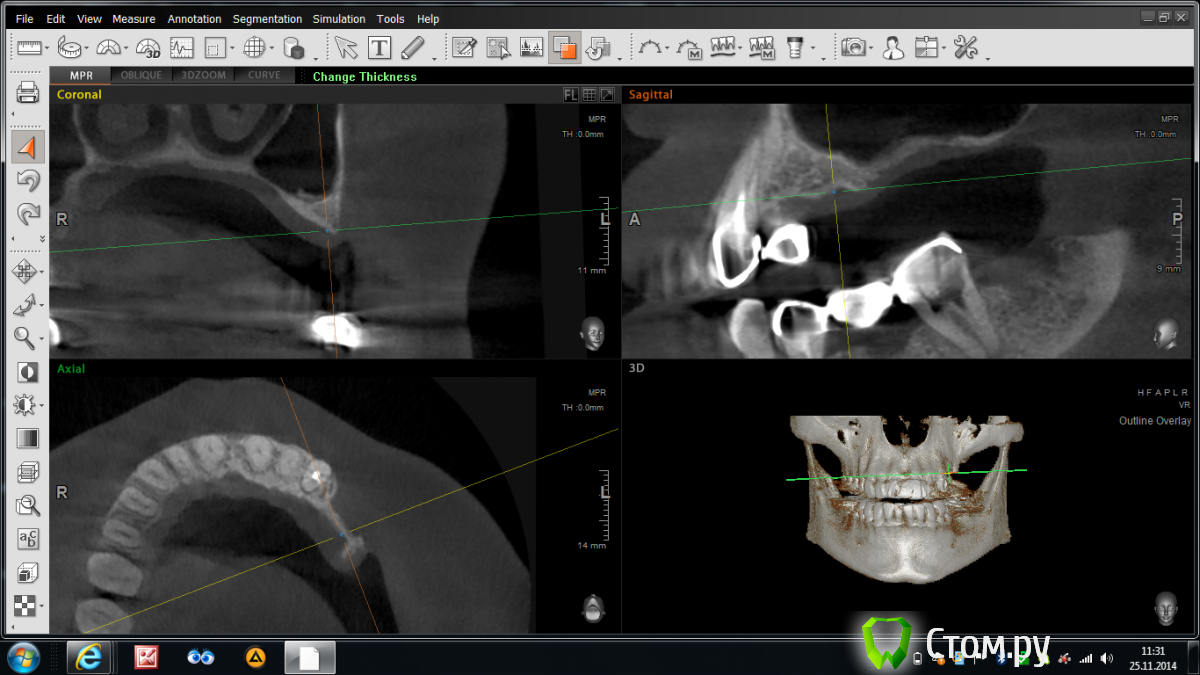

Abuk Опубликовано 25 ноября, 2014 Поделиться Опубликовано 25 ноября, 2014 Доброго времени суток, коллеги. Вопрос ко всем,в частности к Олегу П.Можно ли в такой ситуации восстановить гребень ляминой с тентовыми винтами?Если нет , то какие будут предложения.Планирую вместе с синусом. Ссылка на комментарий

Bier Опубликовано 25 ноября, 2014 Поделиться Опубликовано 25 ноября, 2014 Можно, можно и без тентовых винтов. Продумайте как фиксировать будете чтобы в пазуху не проломиться 1 Ссылка на комментарий